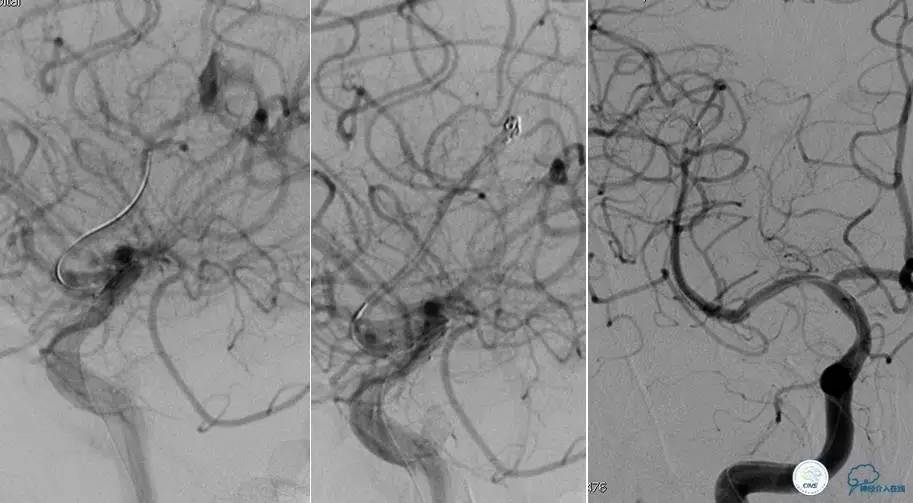

患者:58岁男性,反复头晕、肢体无力3月,当地造影见多发颅内动脉狭窄、闭塞,转来我院。

▼首先行颈动脉CTO开通术,手术顺利,Wallstent支架。

▼1周后行右侧椎动脉V4段CTO开通术。

▼微导丝穿过狭窄段,微导管造影,小球囊预扩张,2mm。

▼根据血管情况选择较大球囊再次预扩张。

▼置入2枚Wingspan支架,手术成功。

▼术后即刻CT,梗死灶内再灌注出血。

患者无症状,中性治疗。4月21日电话随访,一般情况好,当地CT示出血吸收期。